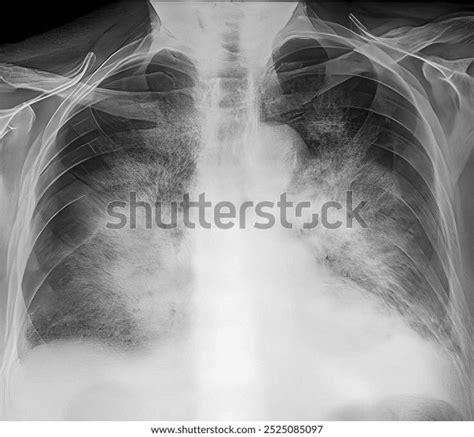

So, what exactly is the batwing appearance we keep talking about? On a chest X-ray, the batwing appearance diagnosis refers to a specific pattern of bilateral perihilar infiltrates or opacities that radiate outwards from the hila (the central part of the lungs where blood vessels and airways enter) towards the periphery, but often spare the very edges of the lungs. Imagine a bat’s wings spread out – that’s roughly the shape this pattern takes, giving it its memorable name. This characteristic finding is primarily associated with acute pulmonary edema , a condition where fluid accumulates in the air sacs of the lungs, making it hard to breathe. When this fluid builds up, it often concentrates in the central parts of the lungs, leading to this distinctive radiological sign. The lung tissue becomes engorged with fluid, appearing dense and opaque on the X-ray film, creating that unmistakable silhouette. This visual cue is a red flag for clinicians, signaling potential heart failure or kidney issues that are causing fluid overload.

But it’s not just about what it looks like; it’s about what it means physiologically. The batwing appearance diagnosis tells us that there’s significant interstitial and alveolar edema, predominantly in the central lung zones. Why the central zones, you ask? Well, it often comes down to gravity and lung anatomy. In many cases of pulmonary edema, fluid tends to accumulate in the more dependent (lower) regions, but in the upright position, the hila are central, and the perihilar region is where much of the initial congestion occurs due to hydrostatic pressure. As the heart struggles to pump blood effectively, pressure builds up in the pulmonary capillaries, forcing fluid out into the surrounding lung tissue. This fluid-filled tissue then absorbs X-rays more readily than air-filled tissue, resulting in the white, opaque areas seen on the radiograph. It’s a powerful visual indicator that helps narrow down the diagnostic possibilities quickly. Recognizing this pattern is the first critical step in making an accurate batwing appearance diagnosis and initiating life-saving interventions. Without a keen eye for such details, precious time could be lost, which is why radiologists and emergency physicians are trained to spot this particular pattern instantly. The pattern can be subtle at first, but as the edema worsens, it becomes more pronounced, making the batwing appearance diagnosis increasingly obvious. Moreover, while chest X-rays are the primary tool for initial detection, CT scans can offer a more detailed view, confirming the presence and extent of the edema and helping to rule out other causes. Remember, guys, this isn’t just a pretty picture; it’s a critical piece of the diagnostic puzzle.